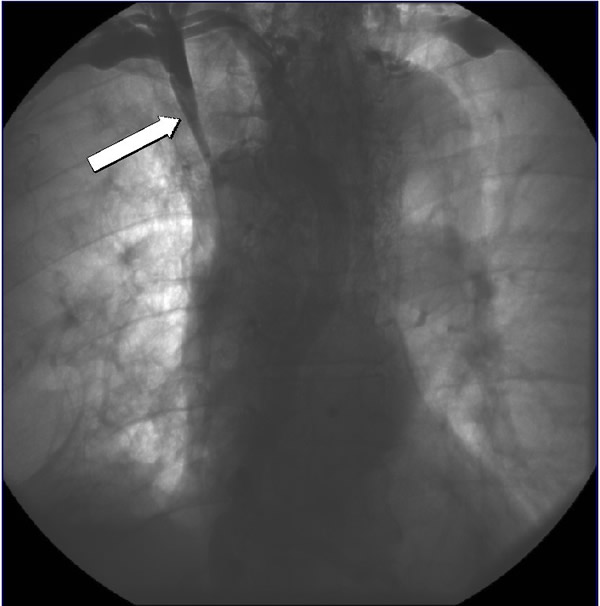

His physical examination was significant for head and upper extremity swelling, jugular venous distention without A or V waves, and superficial varices over the thorax. A computerized tomography (CT) scan (Figures 1A and 1B) demonstrated a mass in the mediastinum involving the superior vena cava (SVC) and extending into the right atrium. Echocardiography confirmed the intracardiac component. The patient was started on neoadjuvant therapy consisting of cisplatin, cyclophosphamide, and doxorubicin with plans for postoperative radiation therapy. A post chemotherapy CT scan demonstrated shrinkage of the mass (Figures 1C and 1D). A preoperative venogram confirmed the occluded SVC and well formed collaterals (Figure 2).